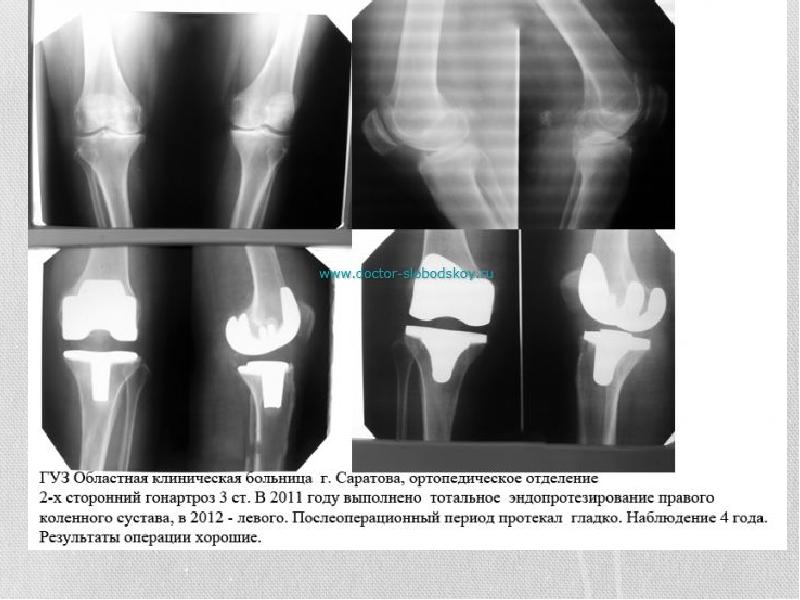

- 10. Гонартроз Гонартрозом или деформирующим артрозом коленного сустава называют дегенеративно-дистрофическую патологию, поражающую